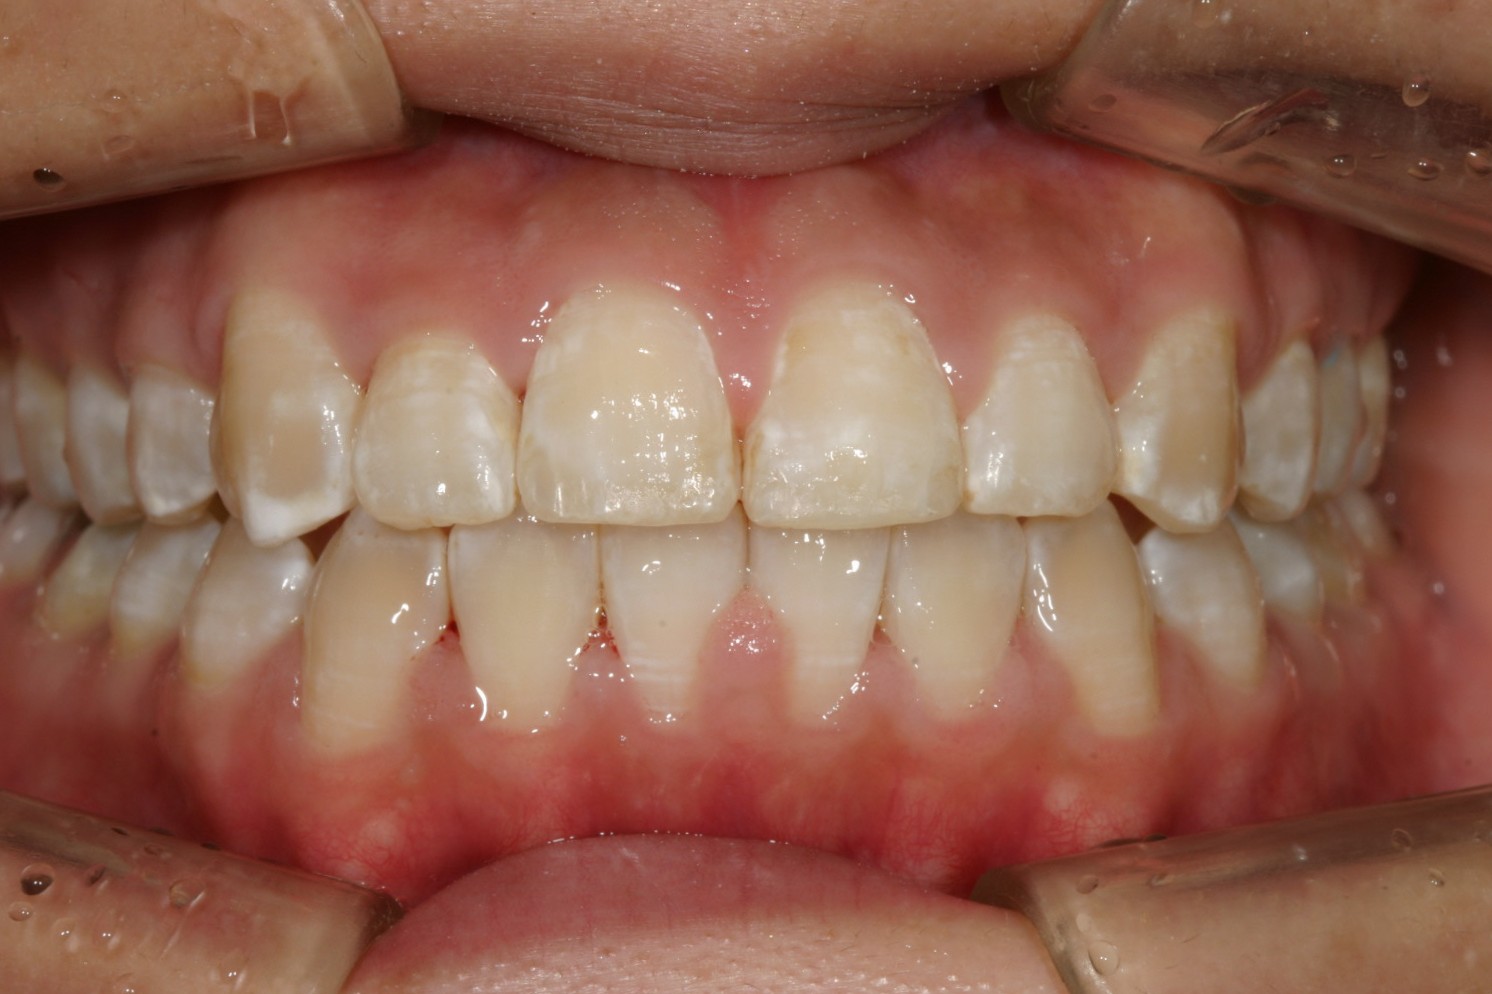

僅か半年でこんなに綺麗に改善しました。

下顎もバッチリ改善しています・

オーバージェットも出来ています。